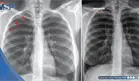

Una tomografía computarizada abdominal mostró un páncreas atrófico con calcificaciones, consistente con su historial de pancreatitis crónica. Dada la bilateralidad del edema, la falta de inmovilidad reciente y la baja sospecha clínica, no se consideró necesario un Doppler para descartar trombosis venosa profunda. Un ecocardiograma transtorácico resultó completamente normal, descartando una disfunción cardíaca como origen de la retención de líquidos.